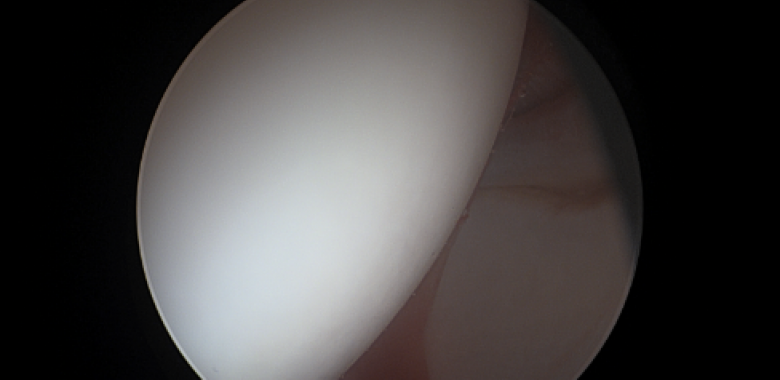

Η ακρίβεια στην οστεοπλαστική στη μορφολογία cam, αποτελεί ένα φλέγον ζήτημα τα τελευταία χρόνια.  Έχουν προταθεί διάφοροι τρόποι για ακριβή αφαίρεση οστού κατά τη διαδικασία αυτή, και υπάρχουν νέες τεχνολογικές και πολλά υποσχόμενες τεχνικές που εφαρμόζονται σε πολλά κέντρα. Ένας προτεινόμενος τρόπος για αυξημένη ακρίβεια είναι το Computer Navigation, το οποίο χρησιμοποιείται σε πολλά κέντρα του εξωτερικού.

Σε μία νέα μελέτη έγινε προσπάθεια να εκτιμηθούν τα αποτελέσματα της χρήσης ενός συστήματος Computer Navigation σε ασθενείς με μορφολογία cam ή συνδυασμό μορφολογίας cam και pincer, και να συγκριθούν τα αποτελέσματα με τεχνική free hand (τεχνική χωρίς ηλεκτρονική βοήθεια).